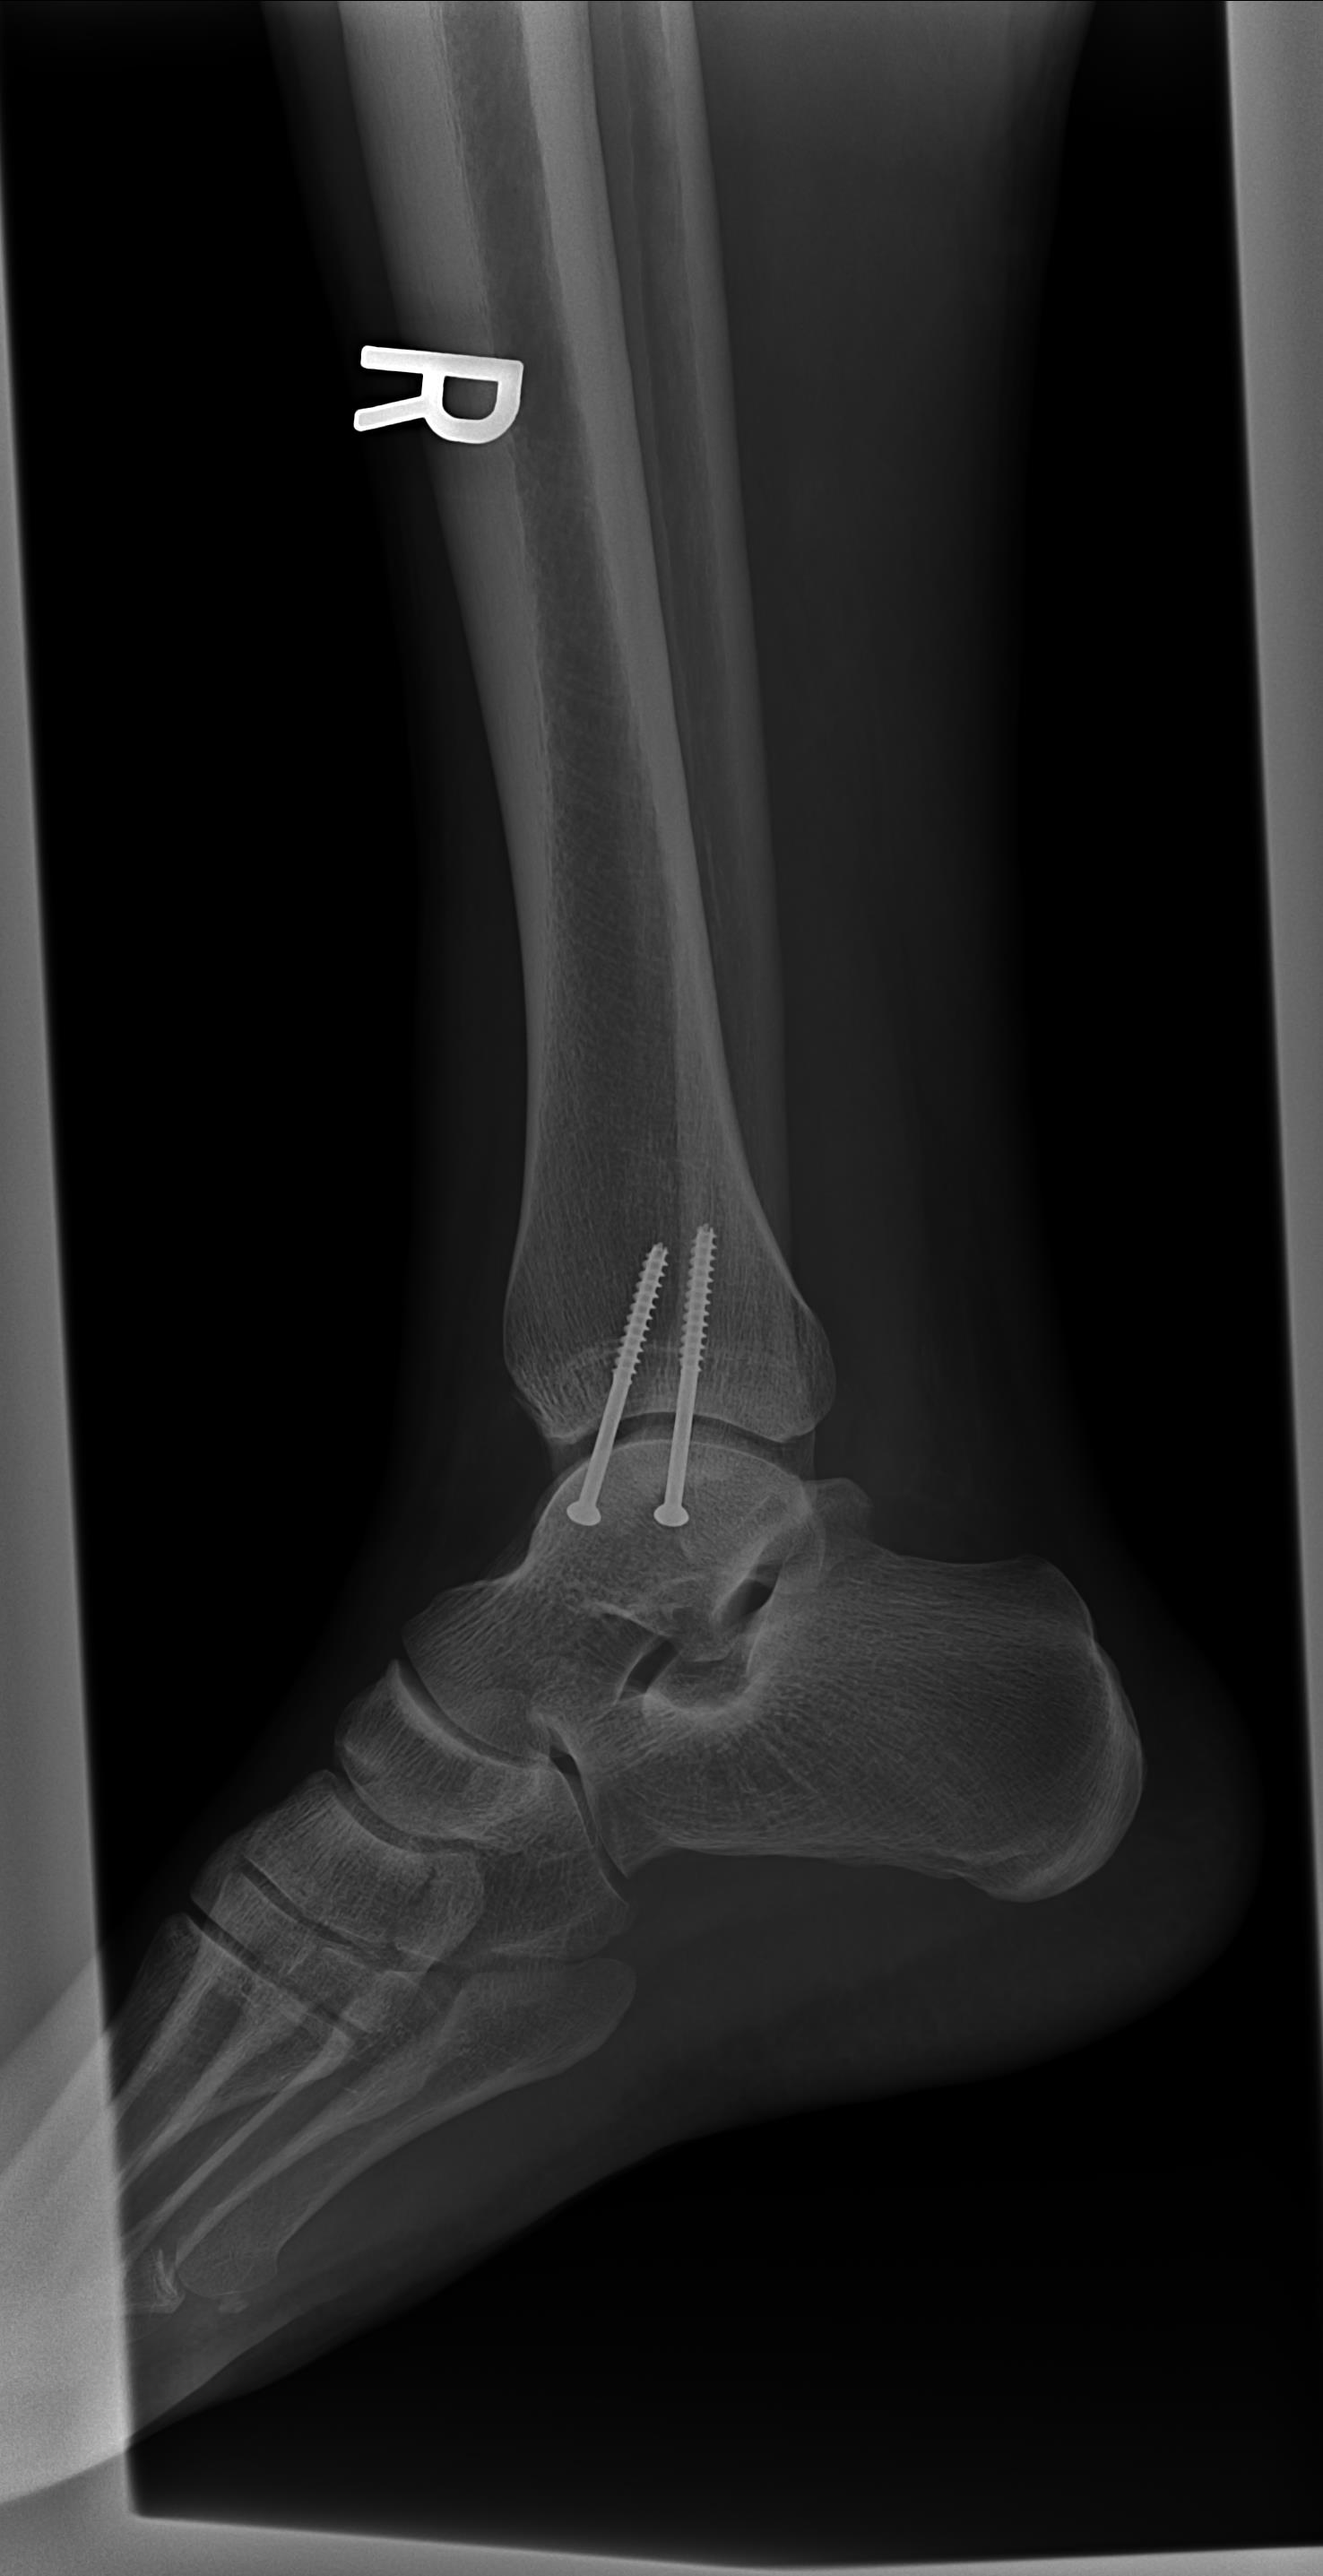

FixedAnkle3